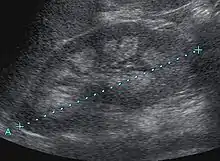

Nephrocalcinosis is diagnosed for the most part by imaging techniques. The imagings used are ultrasound (US), abdominal plain film and CT imaging.[10] Of the 3 techniques CT and US are the preferred modalities.